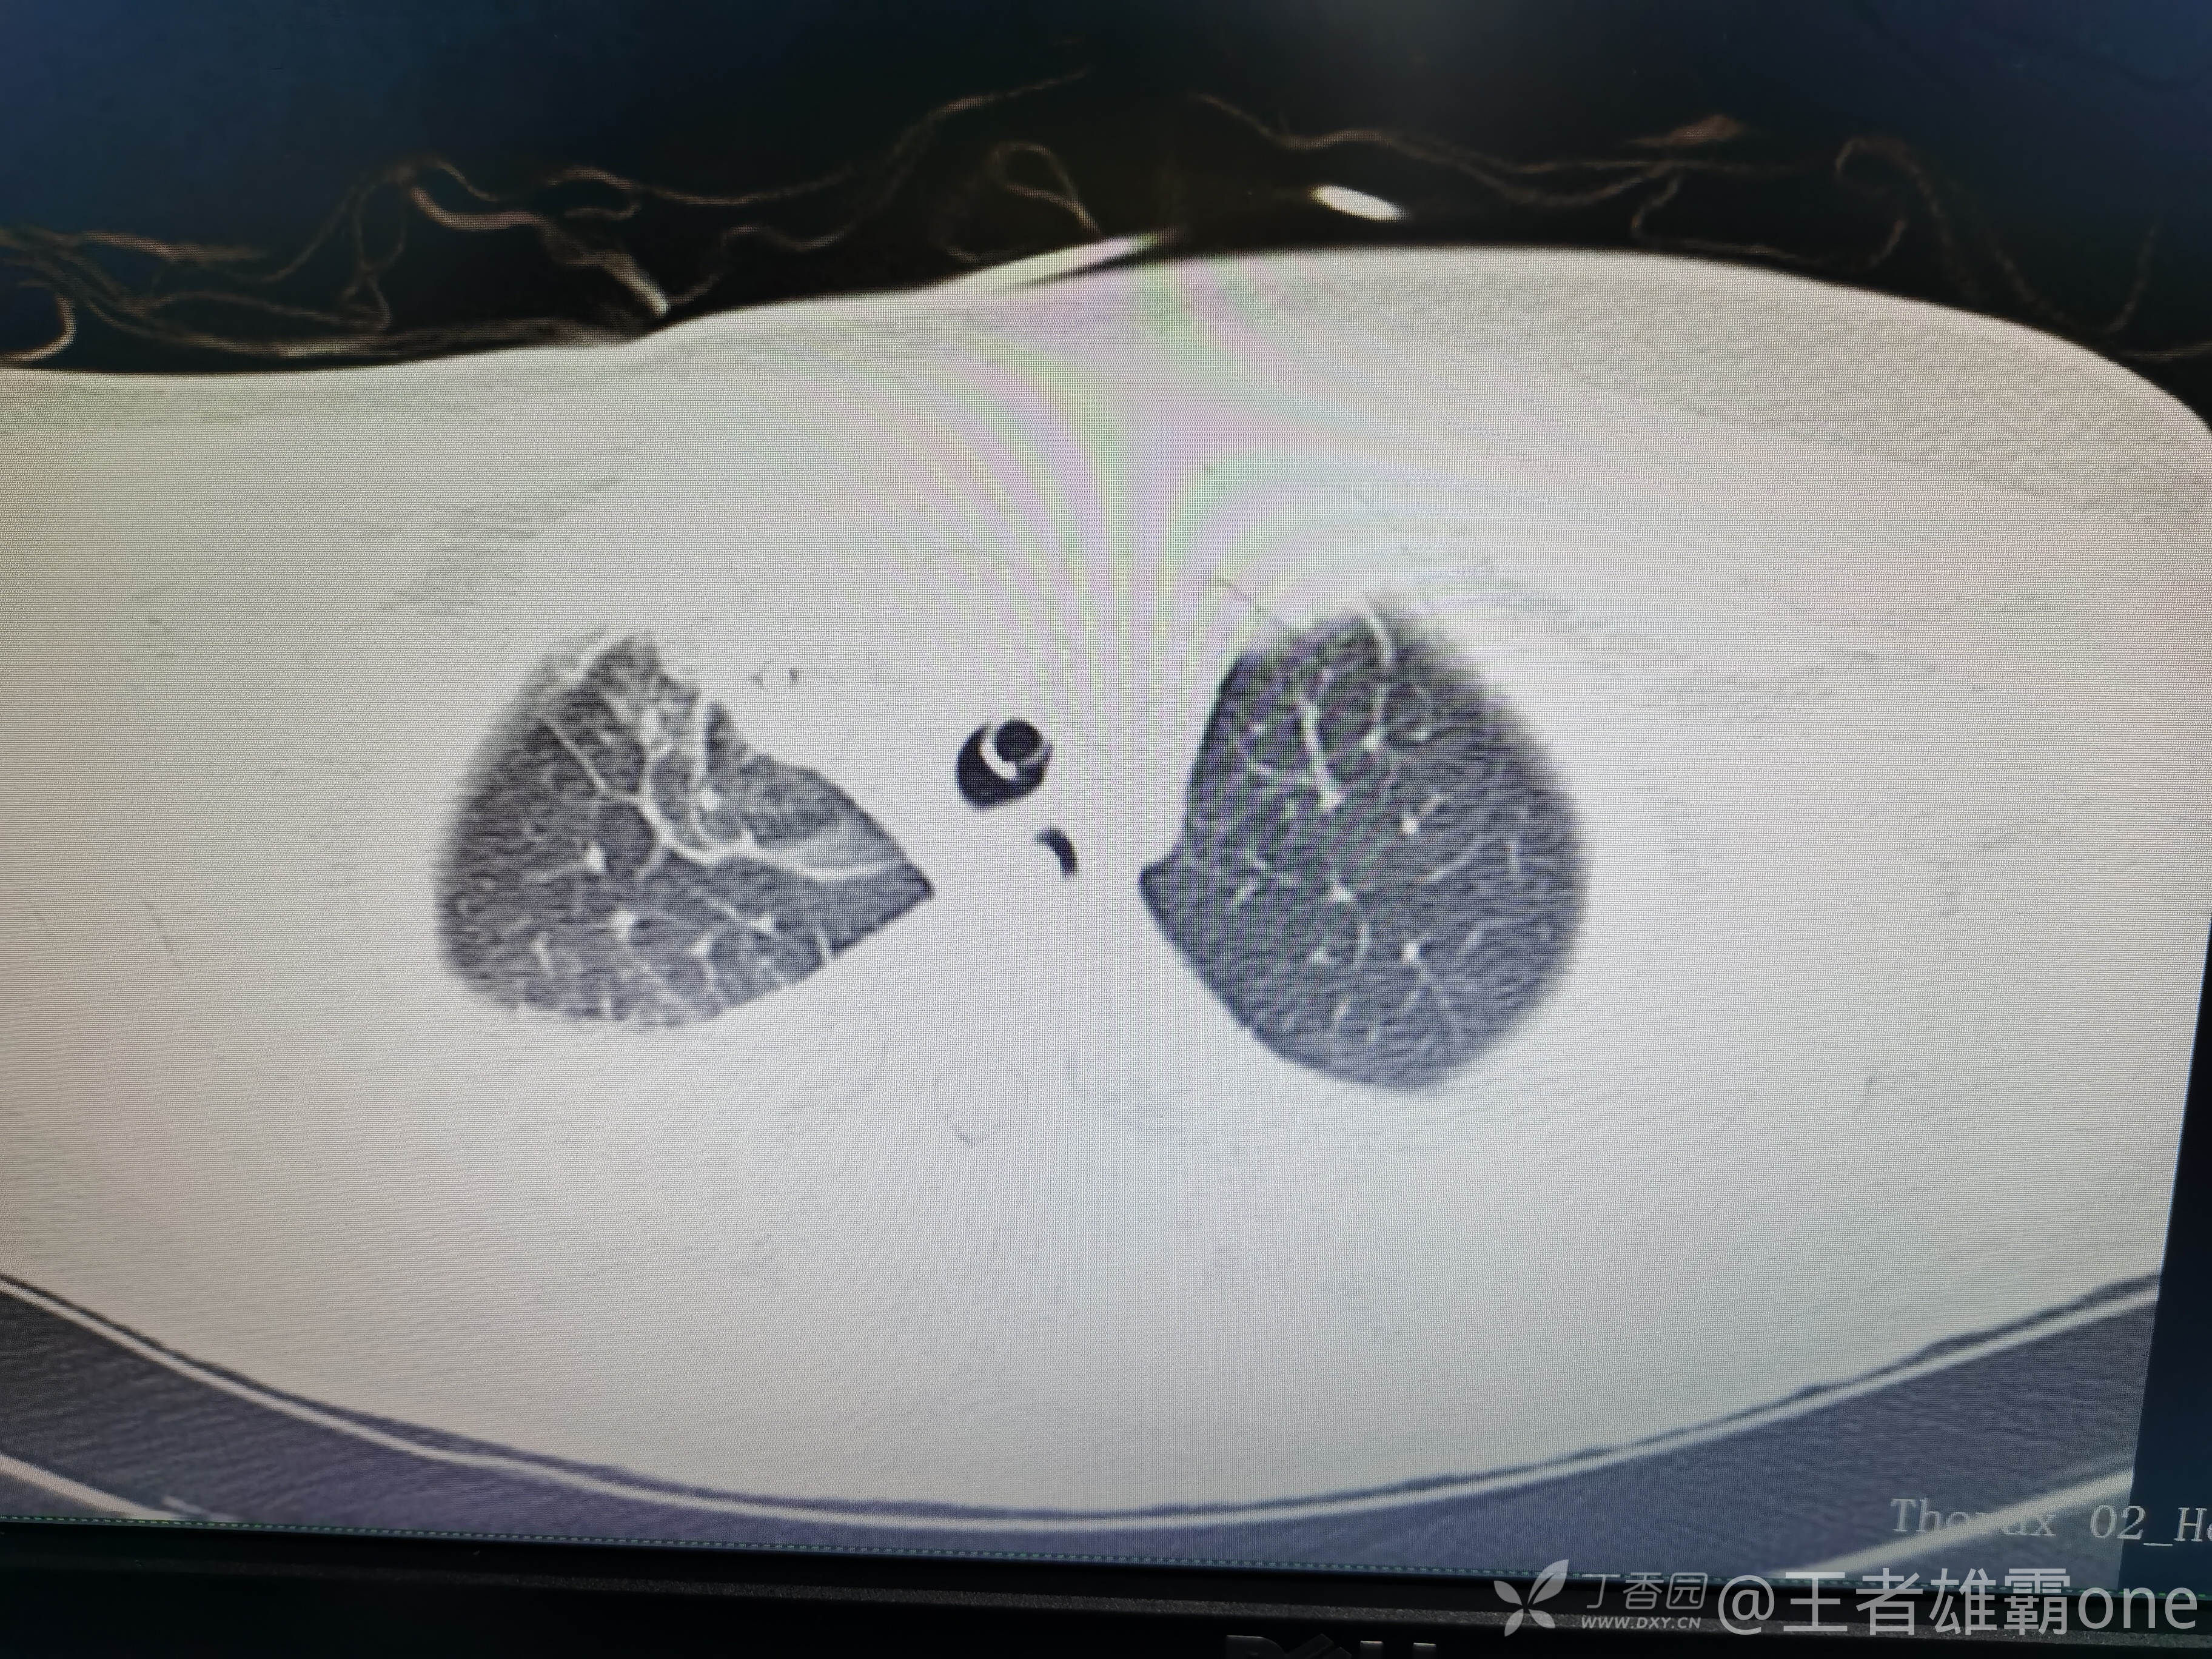

早上复查血常规:血红蛋白100g/L,白细胞11.1×109/L,血小板29×109/L。凝血功能:APTT37.9s,纤维蛋白原3.01g/L,凝血酶时间18.6s,D二聚体21530ug/L。生化:白蛋白36.2g/L,胆红素指标正常,谷丙56U/L,总胆红素38mmol/L,直接胆红素12.1mmol/L,谷草57U/L,肌酐91.1ummol/L,尿素13.97mmol/L,超敏C反应蛋白142.1mg/L。降钙素原17.70ng/ml。脑钠肽前体2164pg/ml。复查胸部CT:

那么问题来了,出现呼吸衰竭气管插管的病因是?请大家讨论分析!